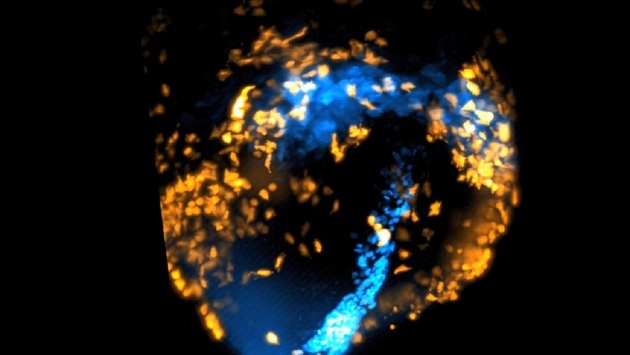

Покадровая 3D-видеосъемка велась внутри живого мышиного эмбриона. Его выращивали в лаборатории в чашках Петри.

Видеосъемка велась с использованием технологии усовершенствованной микроскопии плоскостного освещения. Она позволяет с помощью полосы света вести 3D-съемку, не нанося при этом вред тканям.

Съемка велась в течение 40 часов, а кадры делались каждые две минуты. В результате на них видно, как клетки сердца (кардиомиоциты) заранее помеченные флуоресцентными маркерами, начинают спонтанно организовываться в предсердия и желудочки. При этом их путь можно отследить с самого начала.

Это дает ученым возможность понять, когда и где в эмбрионе появляются клетки, из которых в последующем формируется сердце.